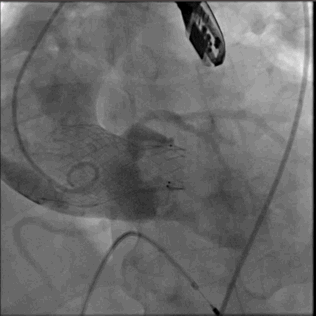

术后随访(一周)

术后讨论

Q1:二叶瓣 合并 横位心 极大增加手术难度

Q2:针对此病例采取 标准位 稍高位 释放